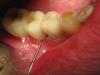

x3m Опубликовано 10 сентября, 2013 Автор Поделиться Опубликовано 10 сентября, 2013 (изменено) чуда, к сожалению, не произошло. сегодня посещение (по поводу расцементировки временного мостовидного протеза 11-23) показало следующую картину в 3 сегменте: обильное гнойно-кровянистое отделяемое (у края десны), грануляционная ткань. у клыка подвижность 2 ст., у имплантата - 3 ст. РВГ: Что видите вокруг имплантата? П.С. Кто знает, каков алгоритм действий в этой ситуации, когда автор-имплантолог находится в Швейцарии?(протоколирование диагностики, манипуляций, подтверждение показаний к удалению и т.д.?) Изменено 10 сентября, 2013 пользователем x3m Ссылка на комментарий

x3m Опубликовано 18 сентября, 2013 Автор Поделиться Опубликовано 18 сентября, 2013 (изменено) протоколирование перед удалением:Алле- -АП! "Удалить за 0,60 сек.": - только что из лунки. на поверхности гной, ошметки кости и чуть свежей крови - видимо, не прижился ... кюретаж, губка в лунку, диплен сверху: ...и рентгенконтроль:смутило наложение тени на пульповую камеру (хочется, чтобы это была костная тень, а не дефект корня с перфорацией). Через 3 дня:подтверждение перфорации (инструменты не цепляют по дистальной стенке, ашка не уперлась ни во что и проскочила почти до апекса): При конденсации кальций тоже не вышел за канал (уф, полегчало): пока 3.3 решили не удалять, наблюдаем. Вопрос по клыку:какой прогноз и какие действия? да, меня вот еще что "несколько смущает" в 4 сегменте:состояние имплантатов в позиции 4.5, 4.6 после установки (апрель с.г.):вид сейчас: МК, шатающийся Clip F в шахте, обратный угол коронок с поднутрением (на фото - зондируем резьбу), там налет и легко кровоточит, язычно над десной - полированная шейка имплантата.а на КТ имплантат 45 в кости на 4мм вестибулярно...как это может работать в долгосрочном прогнозе??? Изменено 18 сентября, 2013 пользователем x3m Ссылка на комментарий